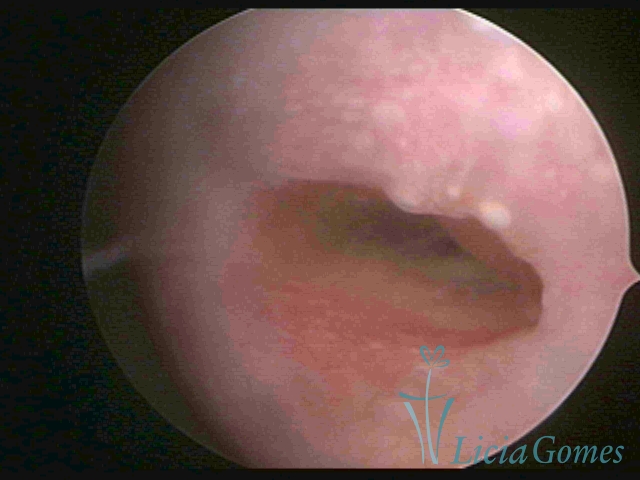

Third part or upper section

Presents the mucosa with a smooth, poorly vascularized surface, to the internal orifice